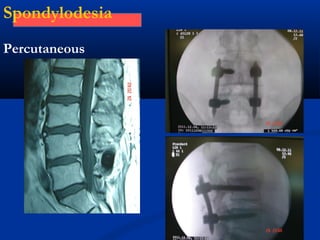

Spondylodesia

Percutaneous

Spondylodesia percutaneous

& Interbody spacer

Percutaneous spondylodesia

and interbody spacer

Post operative

mobilization

following